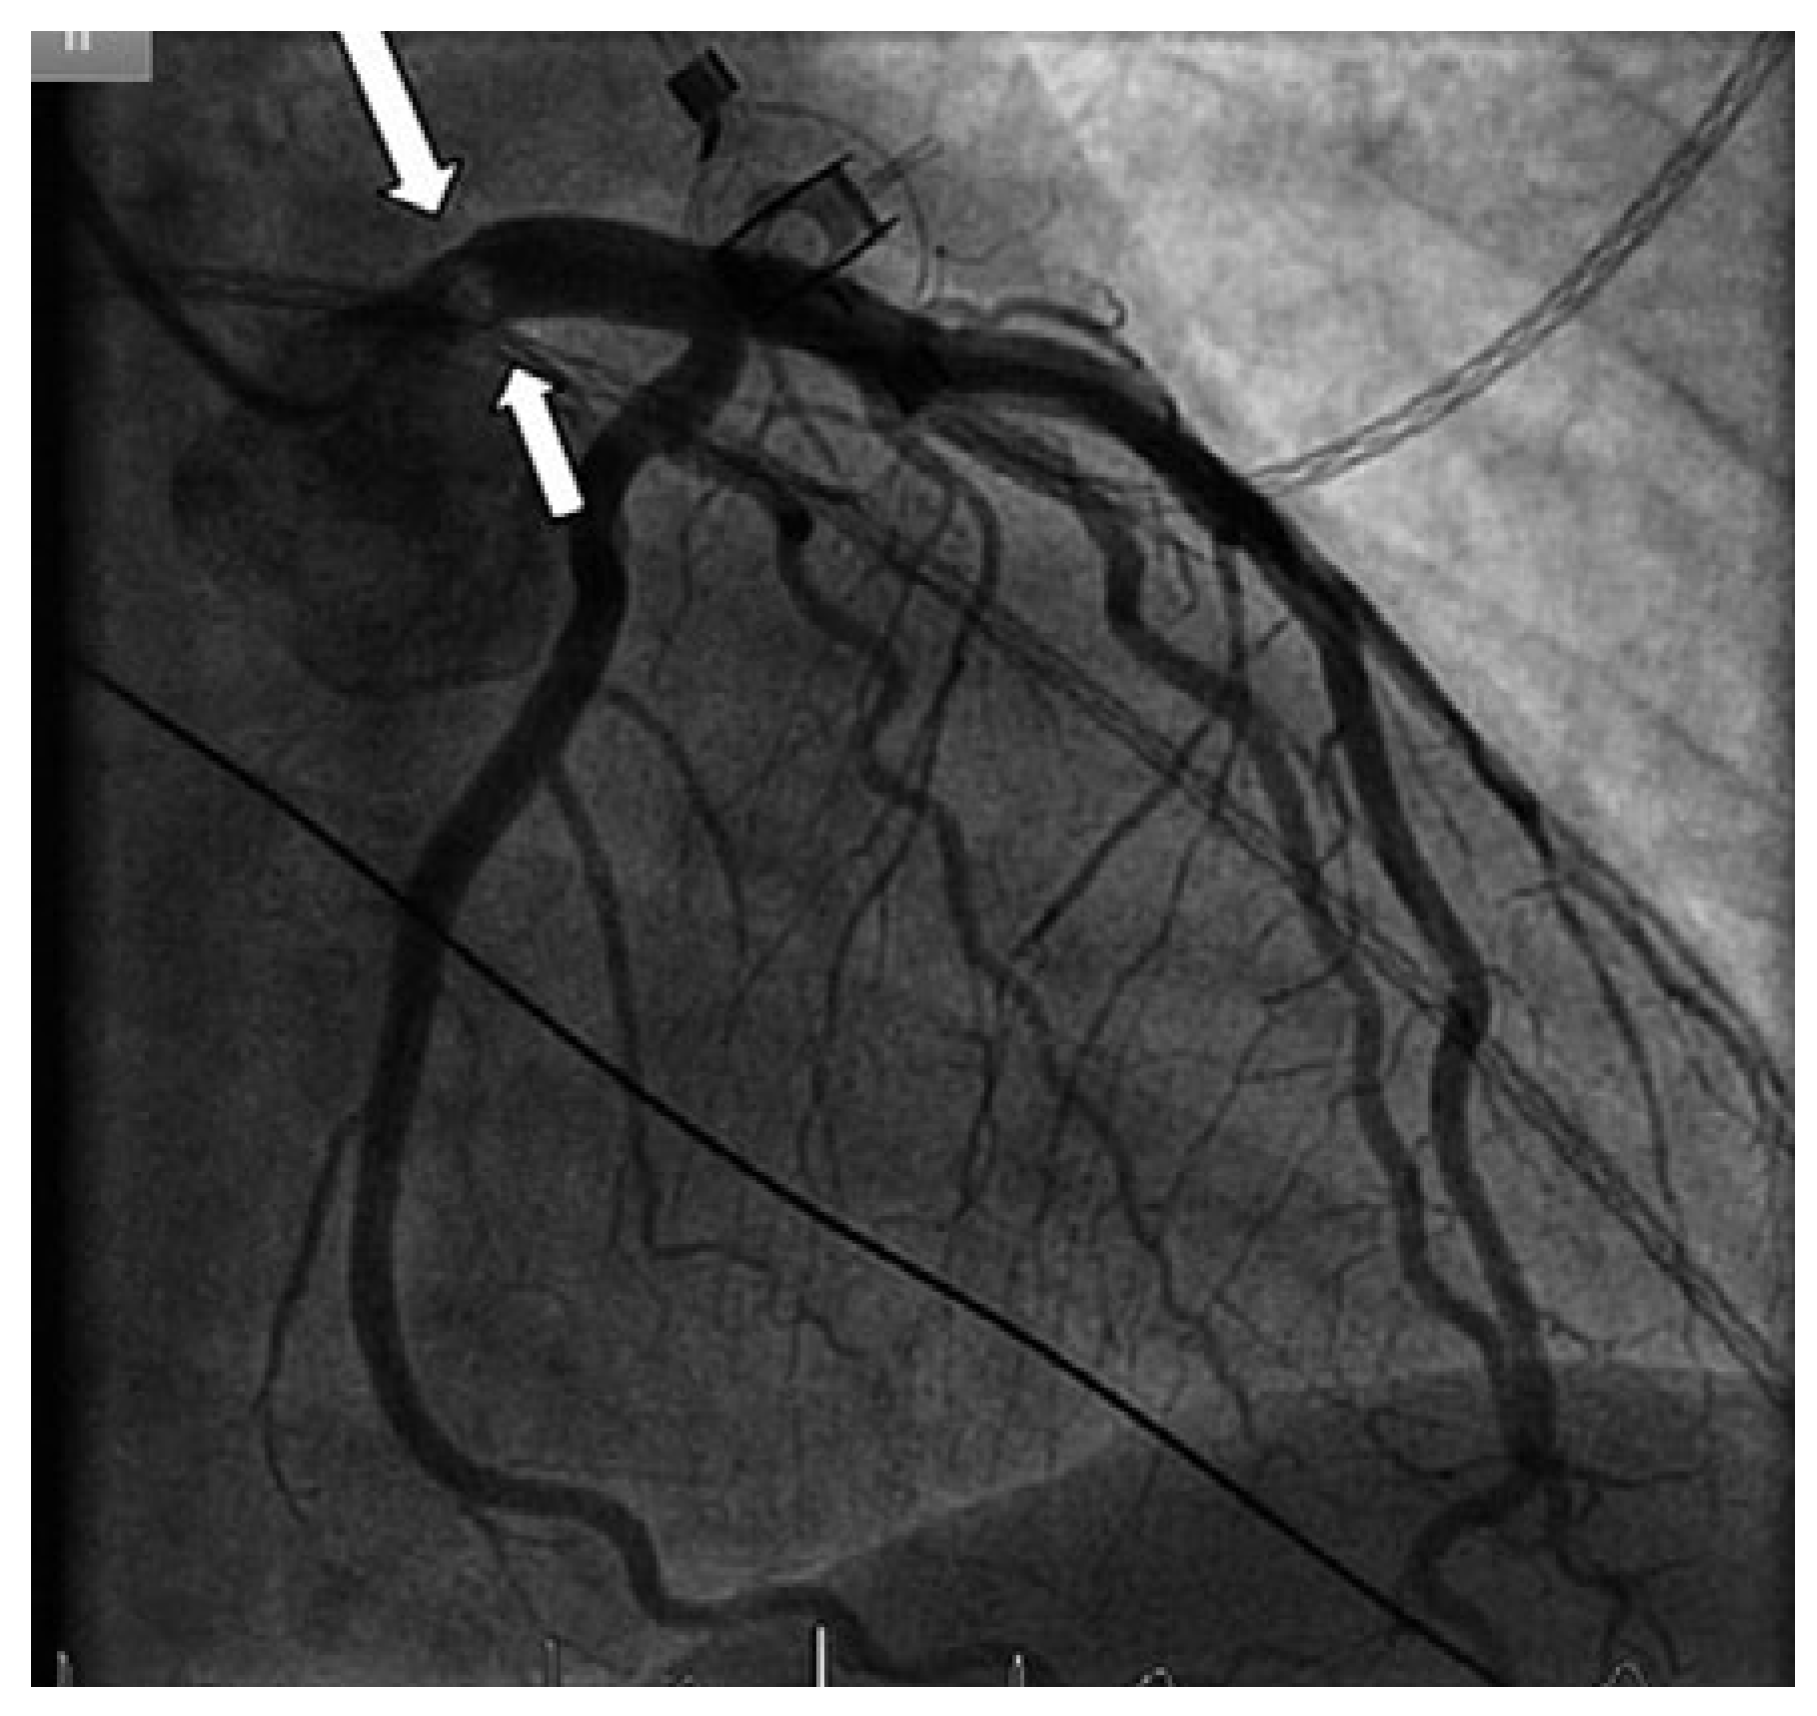

Figure 2.

Coronary angiogram showing a mass protruding partially into the left main coronary artery (arrow), but otherwise normal coronary arteries.